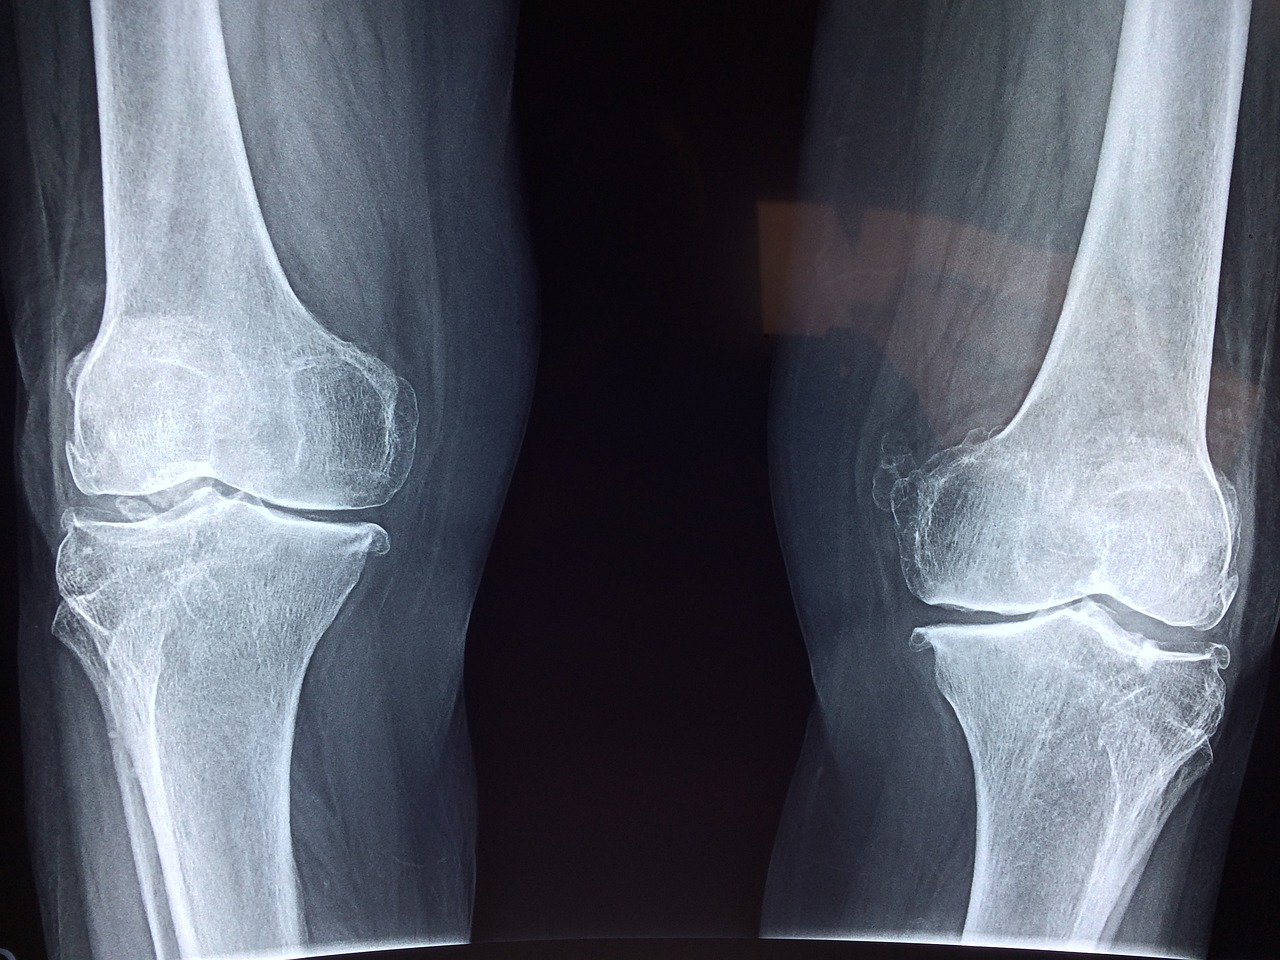

(1) 콘드로이친 효능- 관절건강

콘드로이친은 관절과 연골을 구성하고 있는 성분으로 철갑상어에 많이 들어있다고 합니다. 연골과 관절은 혈액의 움직임이 제한적이고 신경이 없어 손상 시의 회복이 제한적입니다. 콘드로이친은 관절과 연골의 구성성분 중 일부로 콘드로이친을 꾸준히 섭취한다면 연골조직 구성 단백질 생성을 촉진시켜 관절과 연골의 재생과 회복에 도움이 될 수 있습니다. 그렇게 되면 보행능력도 좋아져 잘 걸어 다닐 수 있습니다.

(2) 콘드로이친 효능- 항염

콘드로이친은 체내 염증수치를 감소시키는 효능이 있습니다. 특히 관절염에 효과가 좋다고 합니다. 관절과 연골의 구성성분이 관절과 연골을 강화해 줄 뿐만 아니라 염증도 해소해 주어 '관절엔 콘드로이친'이라는 문구가 생기게 되었습니다. 관절염 환자를 대상으로 한 연구에서 콘드로이친을 6개월 동안 섭취한 결과 전반적인 통증이 감소했다고 합니다.